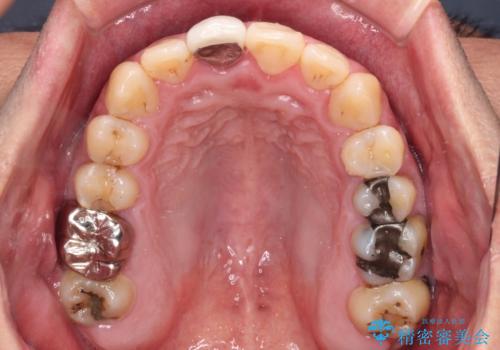

- 前歯のデコボコと上下のクロスバイトを気にして来院された患者様です。

インビザラインを用い、IPR(歯と歯の間を削る)と歯列全体を拡大させることで、歯並びを整えていくこととしました。

上の前歯が下の前歯を乗り越える際、奥歯がほとんど咬めない時期があり、乗り越えた後も、インビザライン特有の奥歯の咬みにくさが続きました。

咬み合わせ改善のために治療期間を要しましたが、最終的に奥歯はしっかりと咬めるようになりました